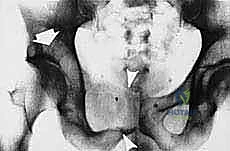

- Plain Radiography (FIG 2): While of limited value for early lesions, it provides an initial overview. As you can see in Figure 2A, we have a large lytic lesion of the right periacetabular region. Figure 2C shows a cartilage-forming lesion in the left ilium. However, plain films often underestimate the true extent of these tumors.